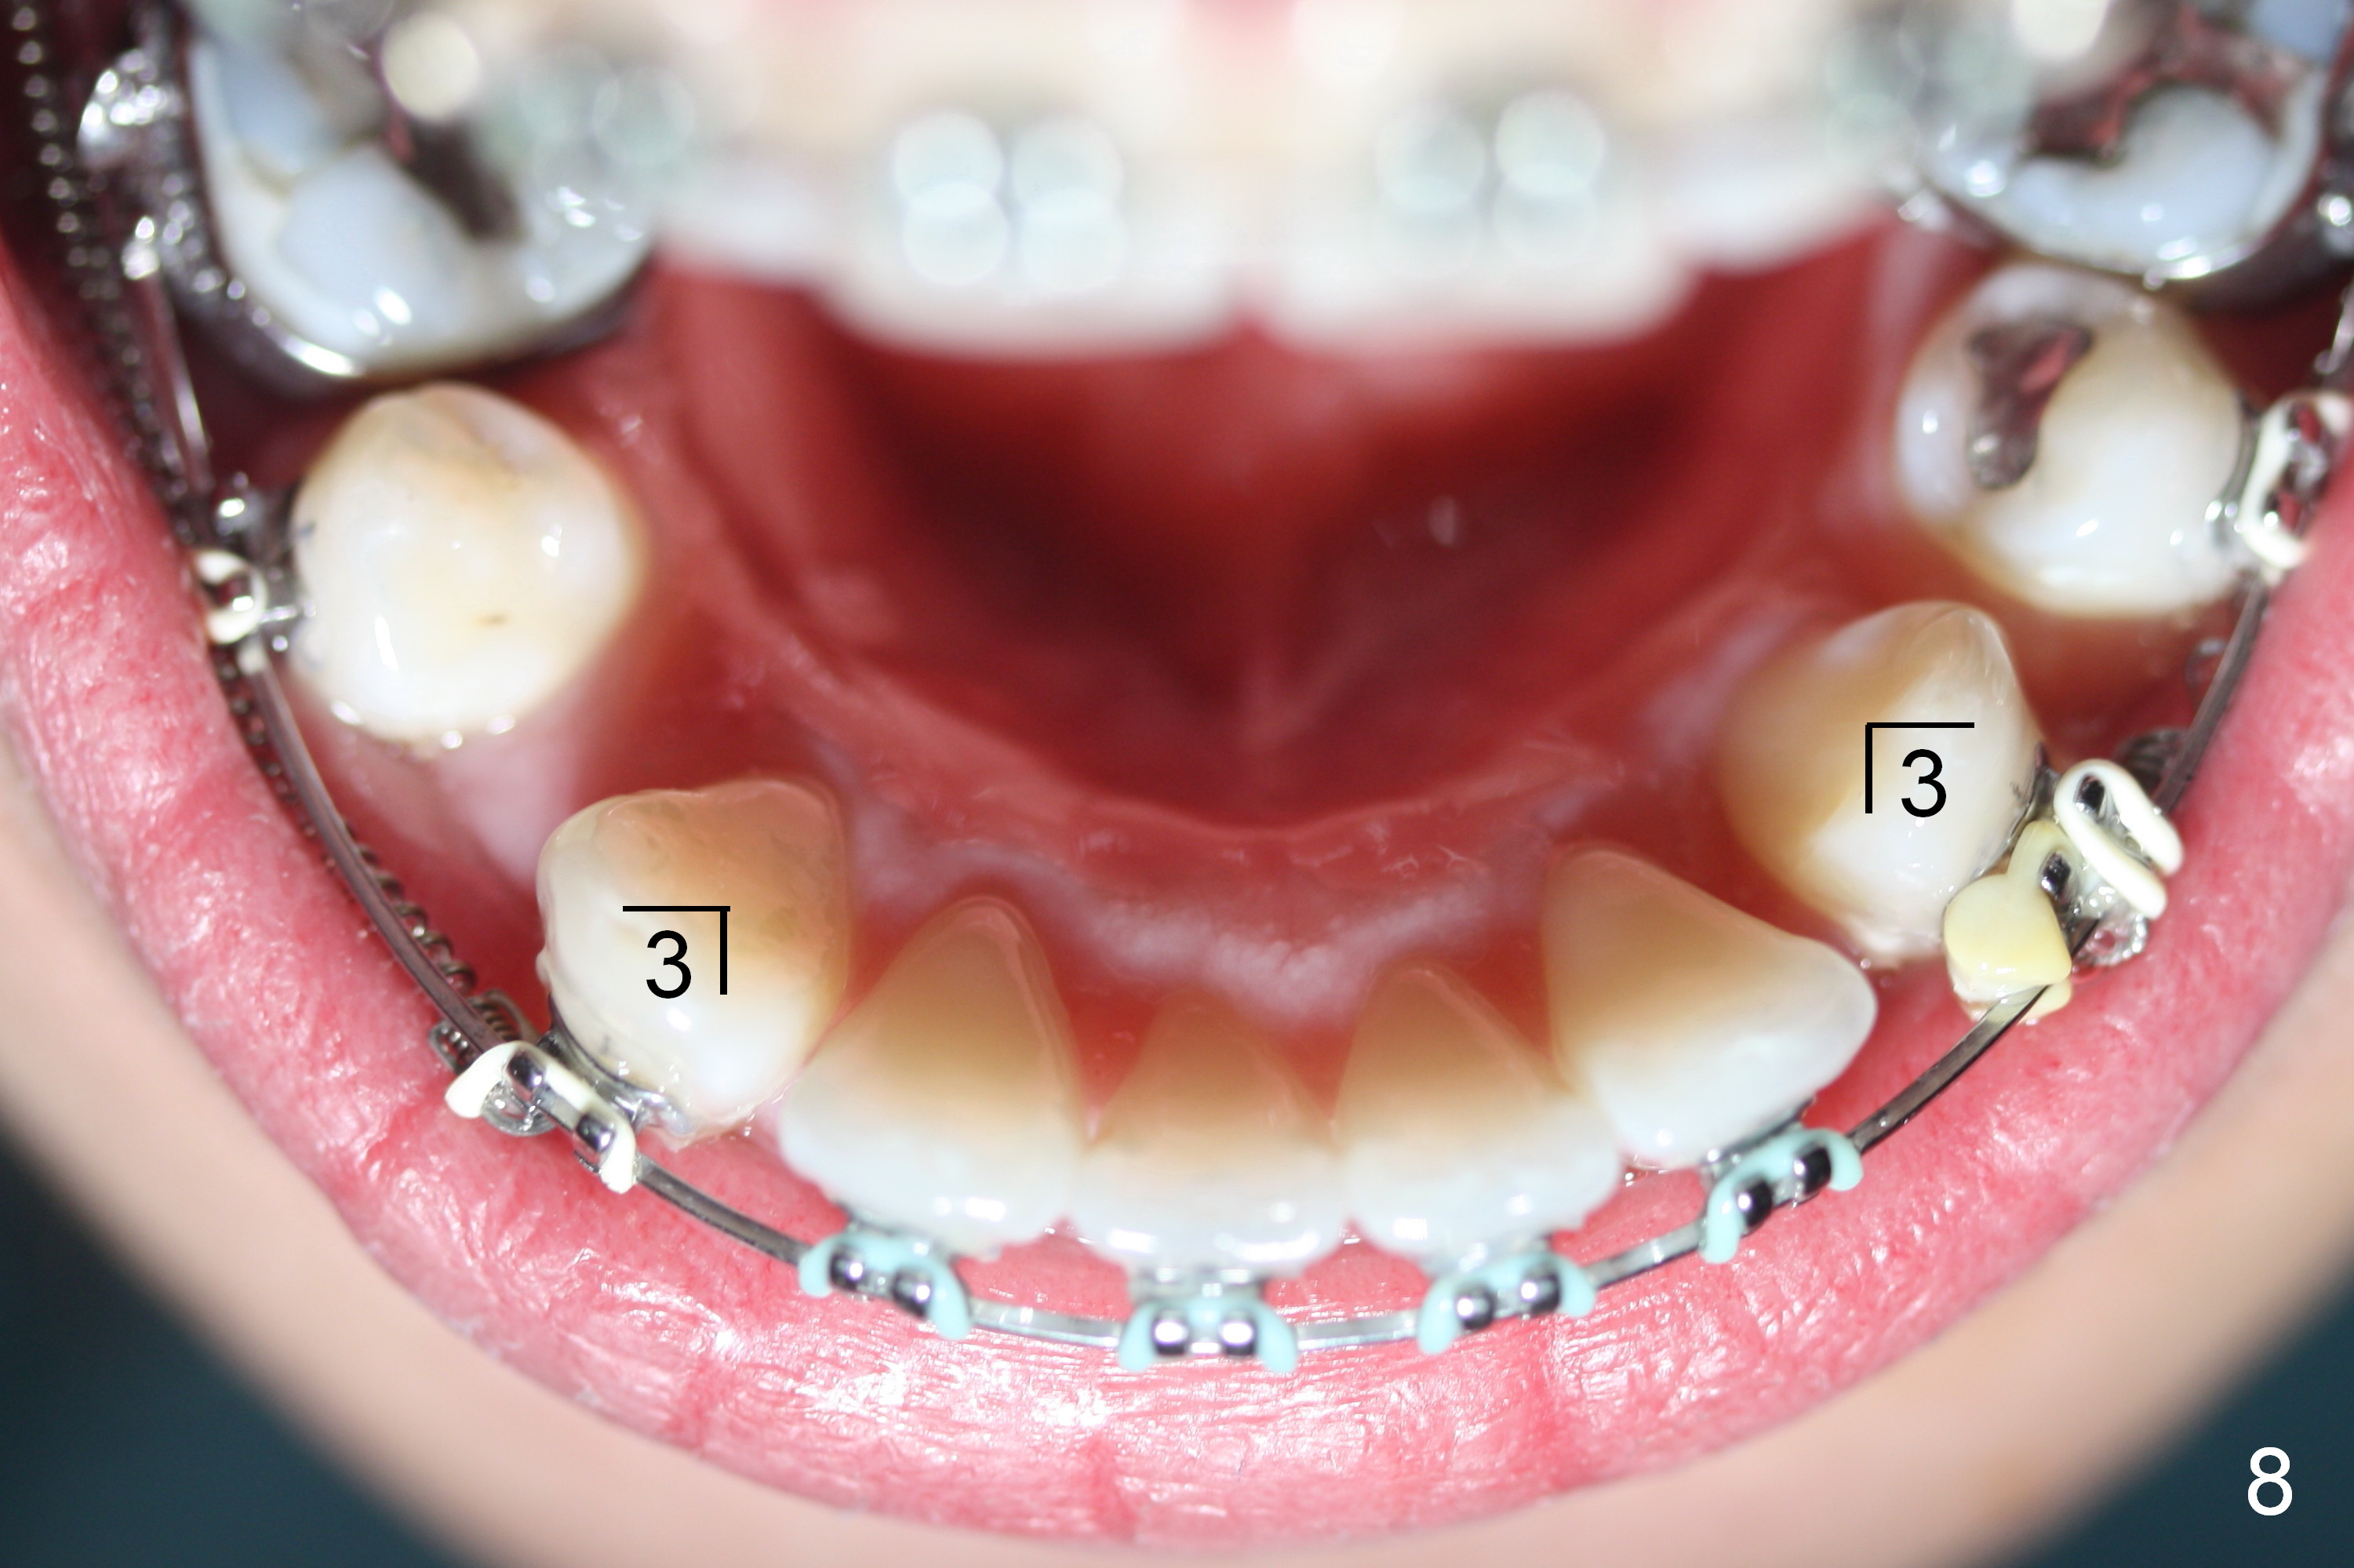

LR 3 shows no sign of distalization the 1st month after placed under closed coil spring (Fig.8), but obvious change occurs the 2nd months (Fig.9,10). Without closed coil spring, LL3 rotation (Fig.5) self corrects (Fig.8), but the tooth bounds back mesially. Closed coil spring is reloaded on LR3 9.5 months of treatment. If L3 are both distalized next visit (10.5th month), use a posted wire to distalize the lower incisors together.